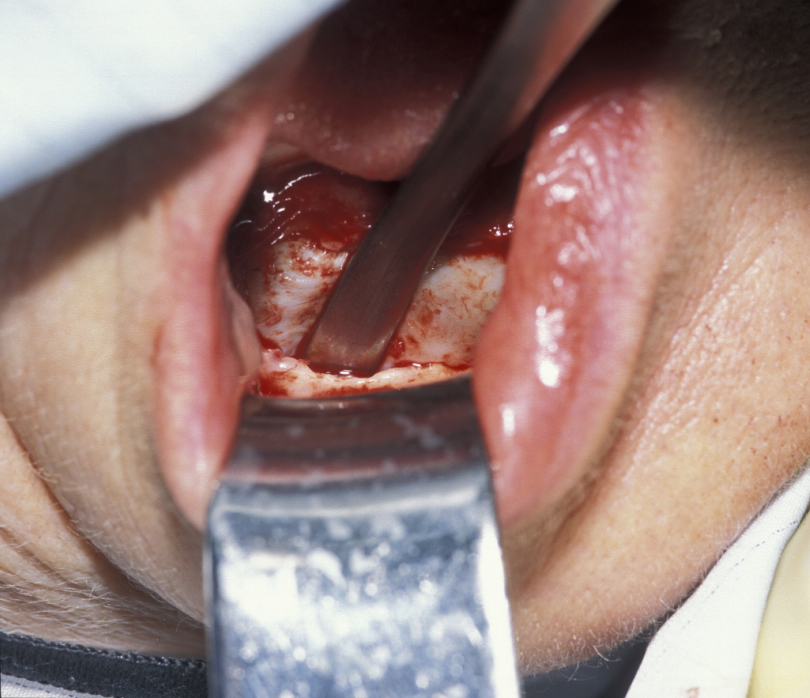

Large cysts in which enucleation may result in extensive local damage or patients who are unfit for more extensive surgery can be managed by marsupialization. This involves exposing the cyst lining and removing a small window from the lining. This is then sutured to the mucosa. The cavity can then be packed with an antiseptic dressing and regularly changed as the cavity heals from underneath. A step by step illustration of the procedure is shown in Figures 7 to 9.

Figure 8: The cyst lining is retained and in continuity with oral epithelium externalizing the cyst.